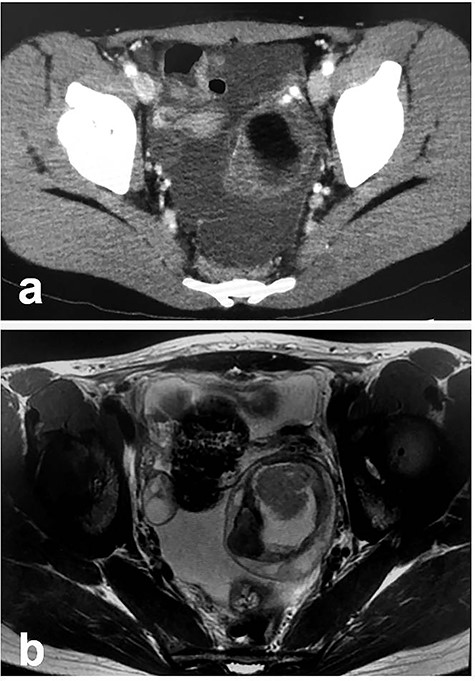

Patient 3: In a 13-year-old girl with abdominal pain, plain CT revealed bilateral ovarian tumors (Fig. 5a: left tumor and Fig. 5b: right tumor). Further examination, including MRI, revealed bilateral ovarian MCTs (Fig. 5c: left tumor; 77 cm × 70 cm, Fig. 5d: right tumor; 115 cm × 90 cm). During laparoscopic surgery, torsion of the left ovarian tumor was released, and each mass was placed in a specimen retrieval bag and removed (left tumor, Fig. 6a–d; right tumor, Fig. 6e–h). Both tumors were large, and content spillage was recognized during surgery. Peritoneal lavage was performed using large amounts of warmed fluid. Pathologic examination of both tumors confirmed the diagnosis of bilateral MCTs. The patient has been doing well without evidence of recurrence. She subsequently established a regular menstrual cycle.

Radiologic findings in Patient 3; (a): Plain CT showing the left-sided tumor (white arrow); (b): Plain CT showing the right-sided tumor (white arrow); (c): MRI showing the left-sided tumor (white arrow); (d): MRI showing the right-sided tumor (white arrow).